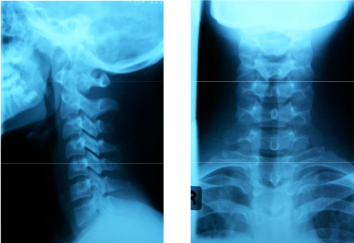

A 12-year-old girl presents to the Emergency Department following a motor vehicle accident complaining of neck pain. She was a front seat passenger wearing a seat belt in a stationary car which was hit from behind by a vehicle travelling at approximately 30 kilometers per hour. On examination she has no bony tenderness and full neck movements with no neurological deficit.

Which of the following best describes the lateral cervical spine radiograph shown above?

A. Fracture C2 pedicles.

B. Fracture odontoid peg.

C. Pseudosubluxation of C2 on C3.

D. Spondylolisthesis of C2 on C3.

E. Anterior wedge fracture C3.

Pediatric pseudosubluxation refers to normal mobility of C-2 on C-3 in flexion which may be so pronounced as to be mistake for pathologic motion; (is normal in children < 8 years old);

Pseudosubluxation may be seen in 40% of children at C2-C3 level and in 14% of children at the C3-C4 level